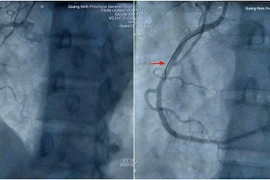

Cứu sống bệnh nhân nhồi máu cơ tim sau mổ nội soi tại Quảng Ninh

Các bác sĩ Bệnh viện Đa khoa tỉnh Quảng Ninh đã kịp thời can thiệp đặt stent, cứu sống bệnh nhân nhồi máu cơ tim đột ngột sau phẫu thuật nội soi.